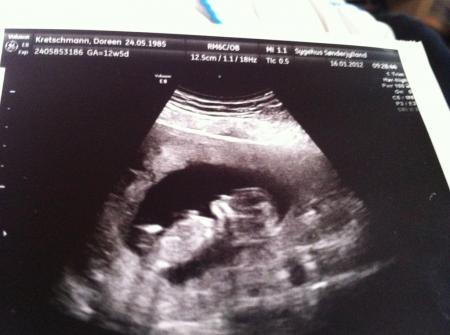

ich sitze hier gerade bei einer sehr guten freundin und habe ihr meine ultraschallbilder gezeigt und sie sagte das ist nen junge, seht ihr auch den schnipel?? Ich sehe ihn und freue mich, was haltet ihr davon... Bitte schnell antworten bin am hippeln :-)

Bild zu schaut mal bitte - Forum für Juli - Mamis

nicht doch das ganz helle... Das weis ich das das die nabelschnur ist ich meine den zipfel in der mitte und kruemel war zu den zeitpunkt 6,3cm